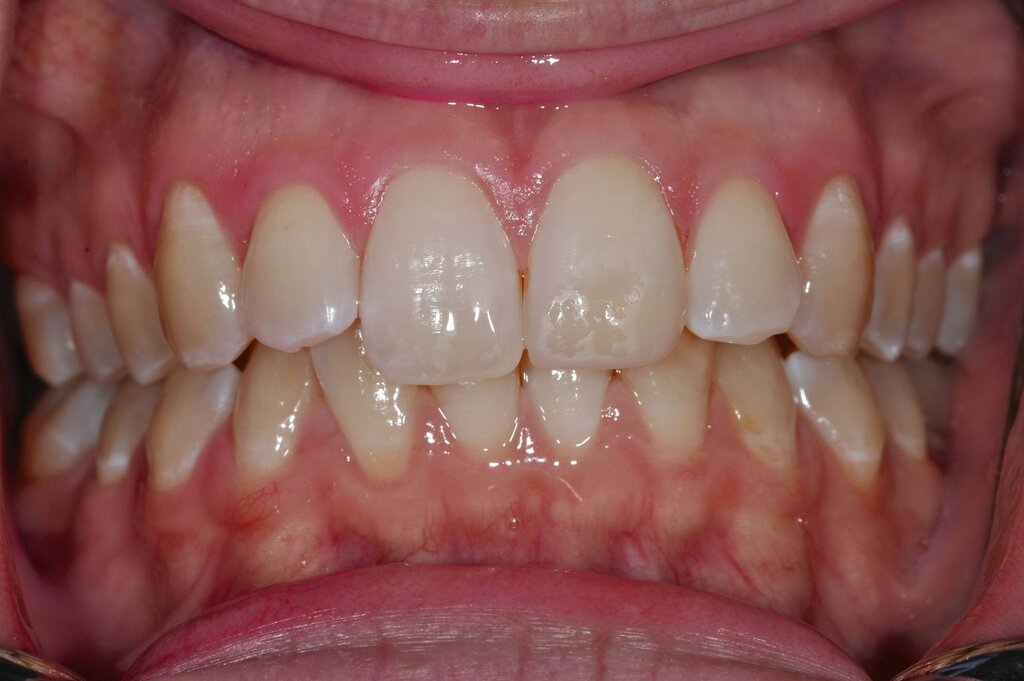

Diese Klassifikation dient als Grundlage für die Therapieempfehlungen. Deutlich wird, dass aufgrund der Symptomatik die Therapie der Zähne höchst unterschiedlich ausfällt. Dass etwa eine Opazität ohne Überempfindlichkeit (Index 1, Abbildung 1) ein anderes therapeutisches Vorgehen erfordert als ein Zahn mit nahezu komplettem Einbruch der Zahnoberfläche und mit Hypersensitivität (Index 4, Abbildung 2), ist offensichtlich.

Für die zahnärztliche Praxis gibt die Einteilung eine Orientierung darüber, welche Behandlungsmaßnahmen erforderlich sind beziehungsweise eingesetzt werden können. Je nach Schweregrad wird dabei zwischen nichtinvasiven und invasiven Maßnahmen sowie einer kurzzeitigen oder längerfristigen, restaurativen Therapie unterschieden. Bei der Überarbeitung des Konzepts wurde zudem zwischen Front- und Seitenzähnen differenziert (Abbildung 3) [Bekes et al., 2023; Steffen et al., 2017].

Die Versorgung der MIH-Frontzähne entspricht dem Vorgehen im Seitenzahnbereich. Problematisch ist die Maskierung der Opazitäten. Dazu müssen opake Komposite verwendet werden und es muss eine Schichtstärke von circa 1,5 mm garantiert sein (Abbildung 9).